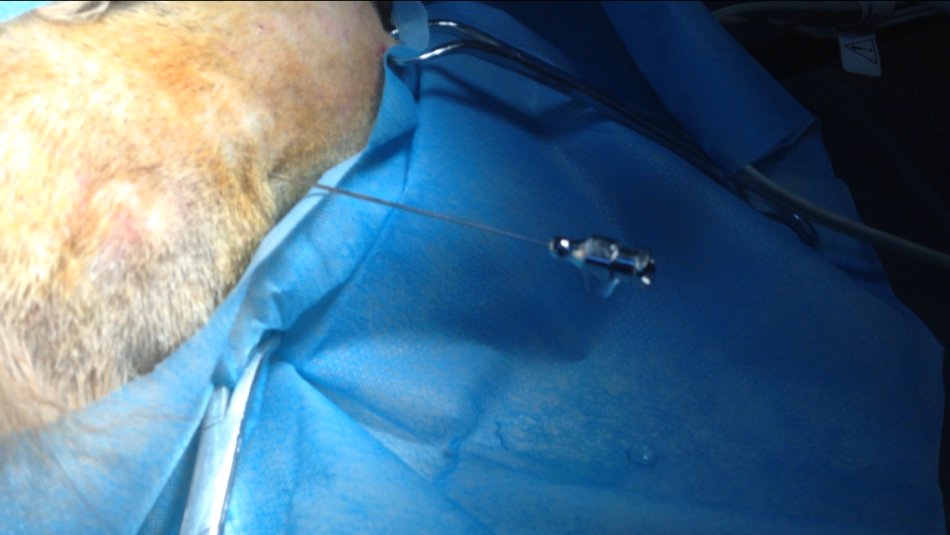

腰部穿刺流出的脑脊液

传统腰椎穿刺脊髓造影小型犬的进针部位为L5L6,大型犬的进针部位也可选L4L5。由于腰部背侧的蛛网膜下腔窄且没有明显的定位标志,一般都将穿刺针穿透脊髓到达腹侧的蛛网膜下腔。定位的标准是穿刺针在抵达下椎管之后稍稍上提2~3 mm。肥胖犬由于触摸脊突困难,难以定位脊髓穿刺部位。同时由于穿刺针抵达椎管的距离增加,使得腰部脊髓造影的难度增大。可以通过透视,脊突部位切开以及预先放置穿刺定位针等方法解决肥胖犬脊髓穿刺困难的问题。